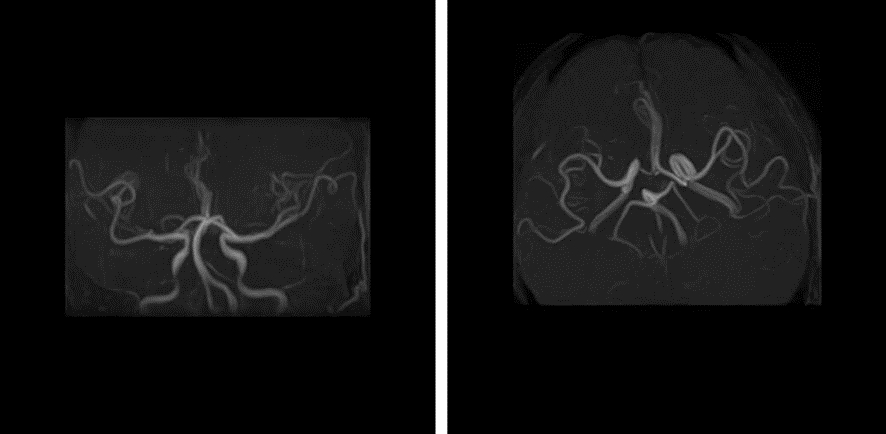

入院辅助检查:血尿便常规、肝功能、凝血功能、血沉、超敏CRP、RF、ASO、输血常规未见明显异常。尿酸 584.0 μmol/L;甘油三酯 1.83 mmol/L。心电图、心脏彩超、颈部血管彩超未见明显异常。MRI显示脑桥上段左侧腔梗灶。DWI显示脑桥上段左侧急性梗死(图 1)。MRA未见明显血管狭窄(图 2)。诊断:脑干梗死,高血压病,痛风。

| 图 2 患者头MRA未见明显血管狭窄。 |